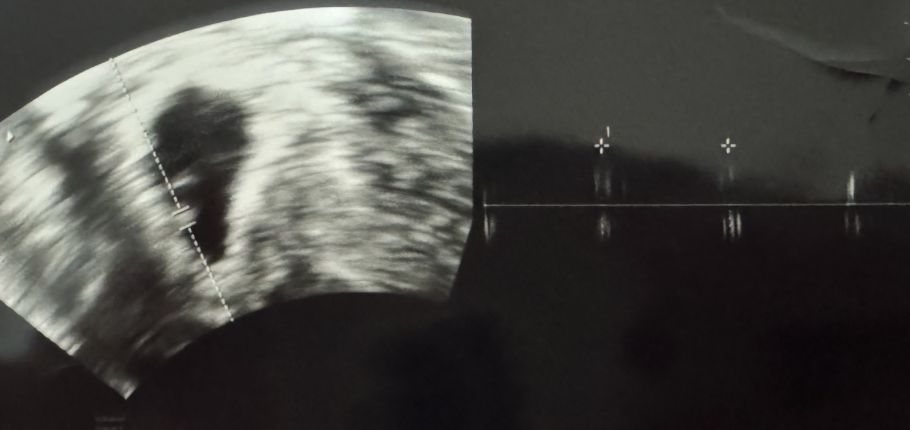

어두운 방 안 초음파 모니터를 통해 우리 찰떡이가 보였다.

"지난번보다 많이 컸어요. 지난번엔 난황이 보이지 않았는데, 이번엔 난황도 보이고 아주 작지만 아기도 보이네요."

초음파 모니터의 한켠에 선생님이 가르키는 위치에 작은 무언가가 보였다.

아기 크기가 0.26cm 였다. 정말 세상에 가장 작은 아이였다.

"아직은 들리지 않겠지만, 심장소리도 한번 들어볼게요"

기계를 통해 측정된 심장박동은 소리는 들리지 않았지만 이것은 분명한 박동이었다.

아직은 심장이 뛰는 속도가 빠르지 않고 성장할수록 점점 빨라진다고 했다.